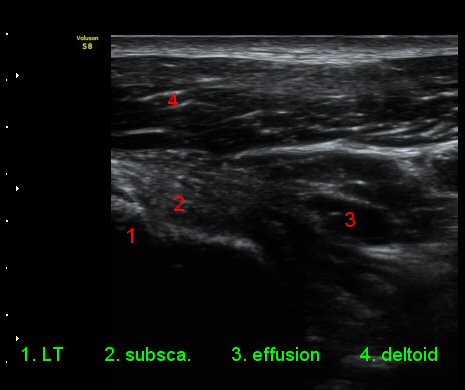

ŽÃÊÀÚ¸¦ ¾à°£ ´Ù¸®ÂÊ, ³»ÃøÀ¸·Î À̵¿ÇÏ´Ï °ß°©ÇÏ±Ù°Ç Ç¥Ãþ¿¡ ¸¹Àº ¾çÀÇ ¼ö¾×Àú·ù°¡ °üÂûµÈ´Ù(»çÁø 3).

ÆÈÀ» ¿ÜȸÀüÇÏ´Ï °ß°©ÇÏ±Ù°Ç Ç¥ÃþÀÇ ¼ö¾×Àú·ù°¡ ´õ¿í È®½ÇÇÏ°Ô °üÂûµµ´Ï´Ù(»çÁø 4).